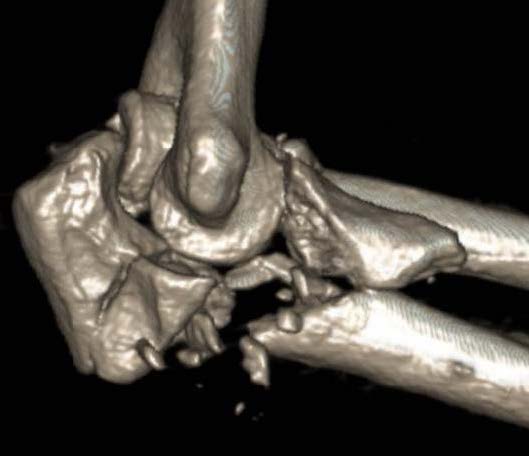

Terrible Triad

Definition

Elbow dislocation with radial head fracture + coronoid fracture + MCL tear

Surgical Algorithm

Principles

1. Restore coronoid stability - ORIF type II / III, suture repair type I

2. Restore radial head stability - radial head ORIF or arthroplasty

3. Restore lateral stability - LCL repair and common extensor origin +/- reconstruct +/- internal brace

4. +/- Restore medial stability - repair MCL if residual stability

5. +/- External fixation / internal joint fixation